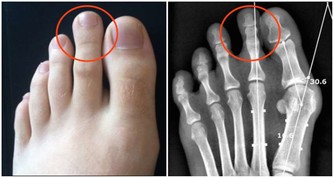

按照物質不滅定律,你使用降血糖藥之後你以為血糖下降了,你就錯了,血糖根本沒有消失,多餘的血糖就開始屯積在你的腳部,就好像糖積在杯底一樣,其結果就是雙足潰爛,你等著截肢吧!前台灣總統蔣經國先生就是受害者,如果你知道此案例,但是你卻沒有學到教訓,還是依樣的重導覆轍,你真是笨死的。